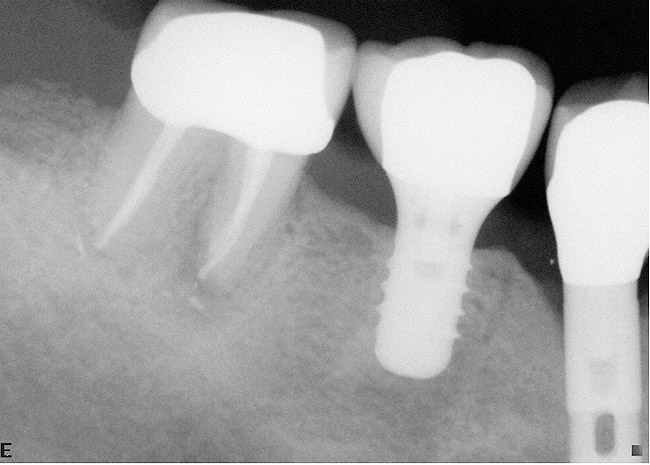

If the most crestal aspect of the interradicular bone is at least 3-mm-wide mesio-distally: A 2.2-mm-wide guide bur is drilled to the appropriate length, a guide pin is inserted, and a radiograph is taken (Figure 7). If necessary, the initial osteotomy is extended apically. A tapered osteotome is inserted into the osteotomy and moved mesio-distally and bucco-lingually to expand the osteotomy site. A 2.8-mm bur is used to prepare the osteotomy to depth, and a 2.8-mm-wide tapered osteotome is inserted in the osteotomy and once again utilized in mesio-distal and bucco-lingual directions to expand the osteotomy site. If the mesial and distal aspects of the interradicular bone are still intact at this point, a 3.5-mm bur is utilized to prepare the osteotomy to depth. A 3.5-mm-wide osteotome is inserted into the osteotomy and utilized in the manner already described. A decision is made as to whether to place a tapered implant with a 4.1-mm-wide base and a 6.5-mm-wide neck, or to use a 4.8-mm-wide bur and prepare the osteotomy to depth, in anticipation of placement of an implant with a 4.8-mm-wide parallel wall body and a 6.5-mm-wide platform. The chosen implant is inserted into the osteotomy (Figure 8), appropriate regenerative materials are placed, and the flaps are sutured. Following maturation of the regenerating hard tissues, the implant is ready for restoration (Figure 9). A radiograph taken 54 months after implant restoration demonstrates stability of the peri-implant crestal bone (Figure 10).